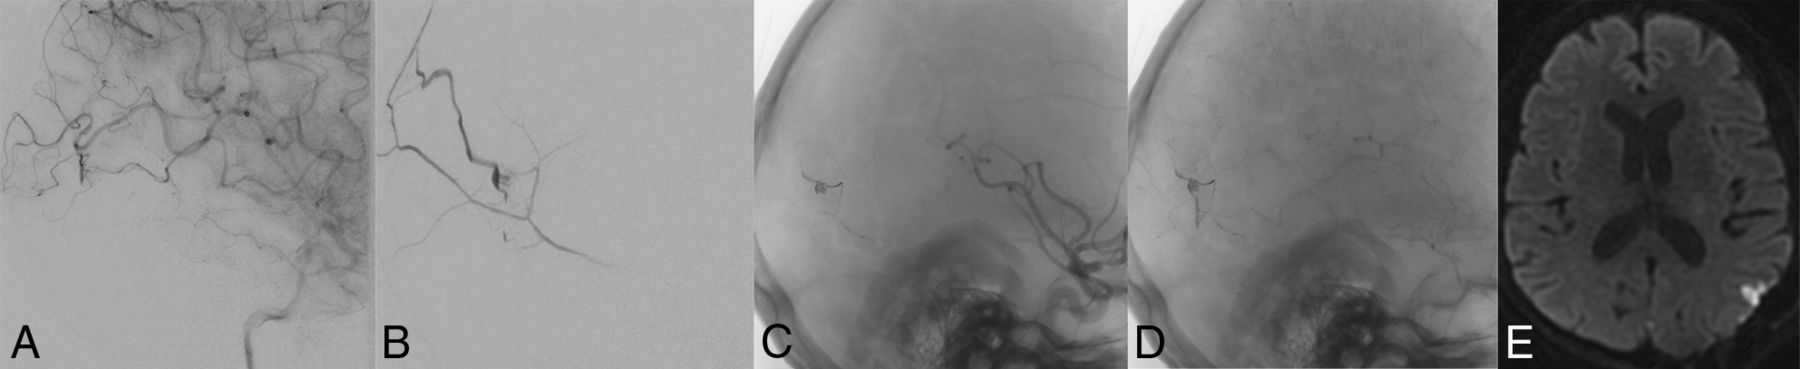

Postsurgical seizure and small cortical infarction after surgical ligation of a residual DAVF. A middle-aged woman status 1 year post temporal lobe hemorrhage underwent endovascular therapy for a Borden-Shucart grade III DAVF supplied principally by the left middle meningeal artery (B) and secondarily by pial branches of the left MCA (A), with drainage directly to a cortical vein. Onyx embolization eliminated the middle meningeal artery dural supply (C), but late-phase angiographic images demonstrated persistent MCA pial supply (D). Three days following a craniotomy for successful ligation of the residual DAVF, the patient had a seizure. MR imaging at that time demonstrates a small cortical infarction (E).